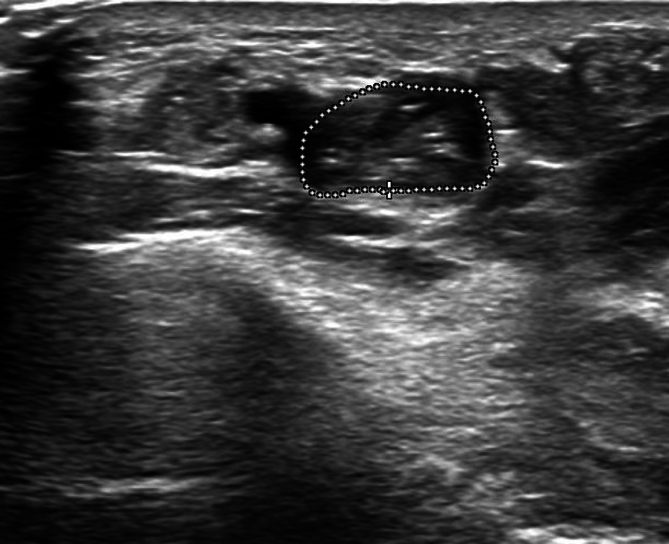

Purpose  Ultrasound (US) has gained in importance for the visualization of morphological changes of injured nerves. After surgical repair, changes in neural structures are seen over time. The correlation of morphologic changes in US with the corresponding nerve function is uncertain. The aim of this study is to determine a correlation of post-traumatic morphological nerve changes with US and with nerve function after surgery. Materials and Methods  This dual-center, prospective cohort study was conducted between 2017 and 2022 and included 20 mixed sensory motor nerve lesions. Patients were followed up clinically (sensitivity, pain, and motor function) with US and electroneuromyography. We determined the US changes of the nerves including the interaction of the tissue after nerve repair and any correlation with nerve function. With US nerve cross-sectional area (CSA), the number of traversing fascicles, hypo-echogenicity, and presence of perineural scar were analyzed. Results  20 lesions (12 median and 8 ulnar nerves) of 18 patients with intraoperatively confirmed nerve injury of at least 50% in the forearm were included. The average CSA was over 20 mm 2 throughout the follow-up period, corresponding to a neuroma in continuity compared to the opposite side (10.75 mm 2 ). Sensibility and motor function at 12 months were 6xS3/4 and 10xM3-5. There was a statistically significant correlation between continuous fascicles on US at 6 months and sensitivity at 12 months. Conclusion  This study supports the presence of post-traumatic morphological changes in nerve fibers with US after traumatic injury. Morphological changes in nerve structure after trauma can be detected with US indicating a correlation between continuity of nerve fascicles and development of sensitivity and motor function.